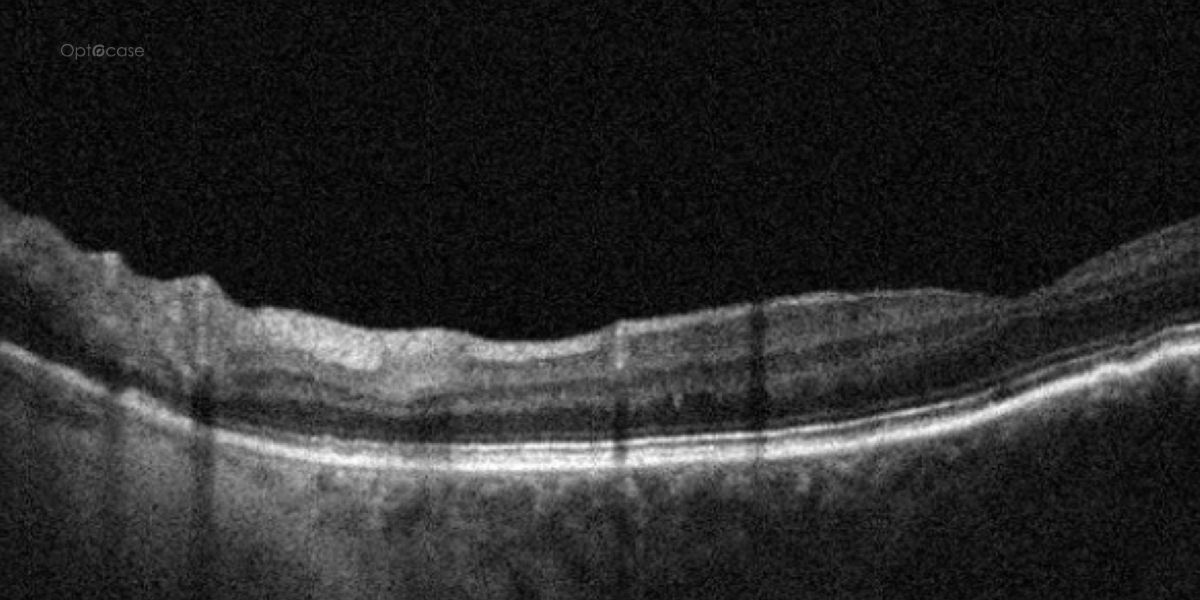

In any patient with intraretinal fluid consider the possibility of an epiretinal membrane causing a schisis.